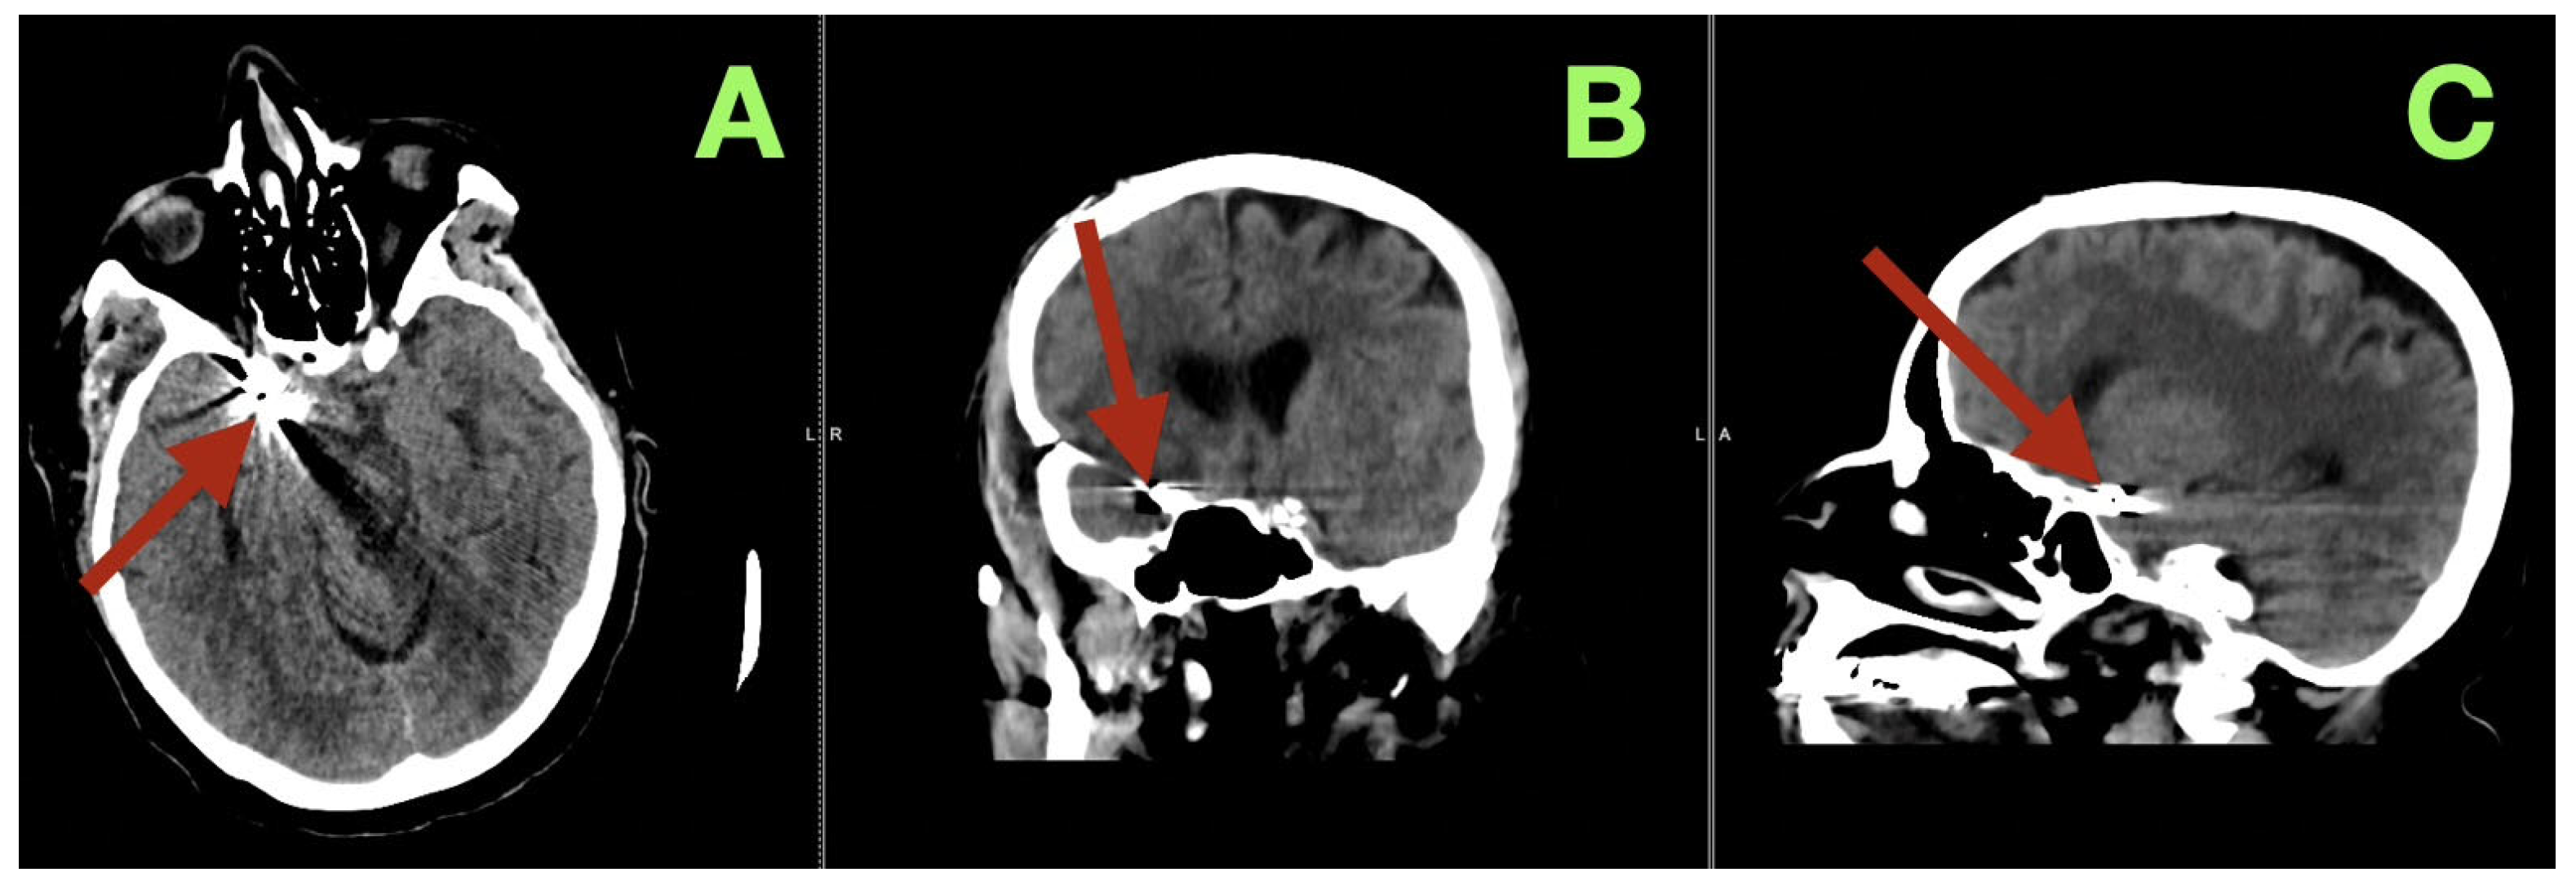

The first image obtained was a non-contrast cranial CT, which showed that there was an SAH (Fisher grade 4), hemorrhage into the ventricles of the brain, and generalized cerebral edema, along with evidence suggesting that the patient had acute hydrocephalus. Due to this verified hemorrhage pattern and significant risk of rebleeding, the patient underwent physiologic stabilization as part of the preoperative process; the patient was intubated and maintained a PaCO2 level between 35 and 38 mmHg to avoid hypercapnic related intracranial hypertension, and the patient’s arterial blood pressure was continuously monitored using nicardipine to keep the systolic blood pressure between 110 and 130 mmHg to decrease the risk of rebleeding while maintaining adequate cerebral perfusion. Selective right internal carotid artery angiography, including DSA, confirmed a saccular aneurysm located at the posterior communicating segment of the right internal carotid artery with a posteriorly oriented dome and a very narrow neck (<3 mm); the aneurysm arose from a branch critical area where a fetal type posterior cerebral artery (fPCA) branched off the aneurysm neck plane (Figure 1A–D). The presence of the aneurysm at a branch critical area made it necessary to reconstruct the junction of the aneurysm neck to the parent vessel, versus simply closing the aneurysm neck to preserve the lumen of the fPCA. Three-dimensional rotational angiography further defined the operative geometry and confirmed the aneurysm’s neck diameter to be approximately 2.5 mm and the maximum sac diameters to be approximately 7.7 × 6.6 mm (Figure 2C,D). The aneurysm was located at the carotid–PCom junction and was closely associated with the oculomotor cisternal corridor providing a potential anatomic basis for the intermittent pupillary variability observed during the acute phase of hemorrhage.

Figure 2.

Three-dimensional rotational angiography reconstructions. (A) Oblique three-dimensional view demonstrates the saccular aneurysm at the right carotid communicating segment (arrow), with posterior dome projection and the aneurysm base seated at the junctional complex. (B) Complementary oblique view highlights the aneurysm’s relationship to the communicating region (arrow), emphasizing the shared plane between the aneurysm base and the posterior circulation outflow tract in the fetal PCA configuration. (C) High-magnification reconstruction provides a quantitative definition of the neck plane, demonstrating a neck width of approximately 2.5 mm (arrow). (D) Quantitative three-dimensional assessment demonstrates maximal aneurysm dimensions of approximately 7.7 × 6.6 mm (arrow) and reinforces the anatomic convergence of the aneurysm neck with the fetal PCA origin, the critical determinant of junction-preserving exclusion.